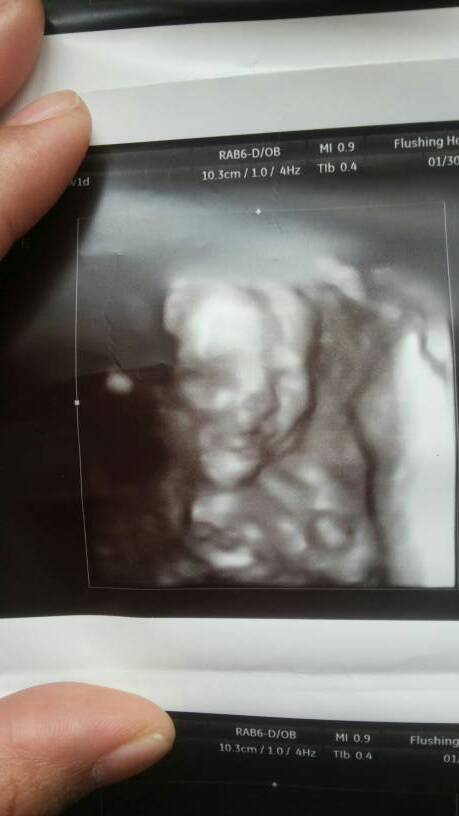

20周做了三维排畸检查,医生说挺好,但是回家我看宝宝有两张照片总觉得有点像唇裂,另外两张好像又没有

20周做了三维排畸检查,医生说挺好,但是回家我看宝宝有两张照片总觉得有点像唇裂,另外两张好像又没有,担心。

你好,你应该是太担心了。医生检查说没有异常应该就没有问题。医生在看的时认航丰候是动态的,可以多个角度来看,一般来说做出的诊断比较可靠。我们看到的报告单上的图片是个静止的,看蔑敢影像可能会受到角度的影响,不能做出明确诊断。如果实在不放心,可以在以后的孕检中让医生再多注意一下胎立贵儿的颜面部。